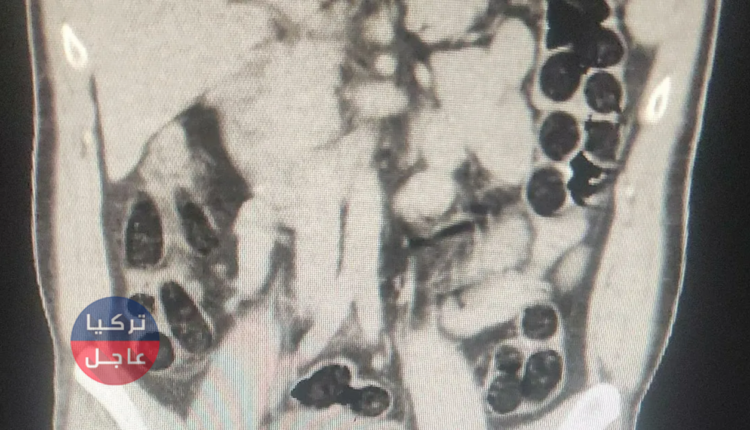

تعرضت مدينة تطوان في ولاية بيتليس التركية لصدمة جديدة بعد اكتشاف كمية كبيرة من الميثامفيتامين في معدة راكب أجنبي على إحدى الحافلات، وكان الاكتشاف ممكنًا بفضل تقنية الأشعة السينية التي أظهرت وجود 550 جرامًا من المادة المخدرة في شكل 73 كبسولة.

وبعد إيقافه وتفتيشه، تم نقل الراكب إلى المستشفى لإجراء فحص طبي، حيث تم التأكد من وجود مواد مخدرة في معدته وأمعائه. الأطباء قاموا بإعطاء الراكب العلاج اللازم، مما أدى إلى إخراج 550 جرامًا من الميثامفيتامين بشكل طبيعي.